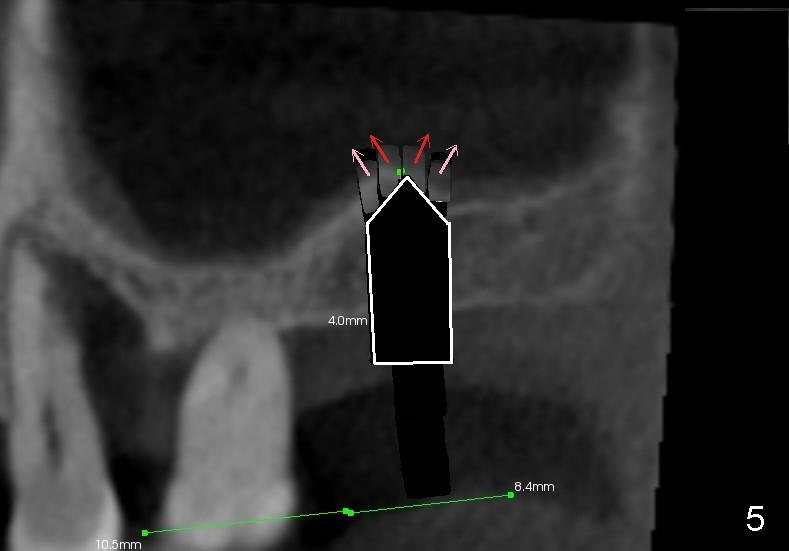

As the diameter of osteotomes increases (from 2, 3 to 4 mm), more of sinus

floor undergoes green stick fracture (Fig.5 pink arrows). At the same

time, more bone is brought apically (not shown). Finally a tapered

osteotome with flat end or tap is used to further lift the sinus floor (Fig.6

white arrow). This time the fractured bone fragments (red and pink arrows)

are more or less at the same level.